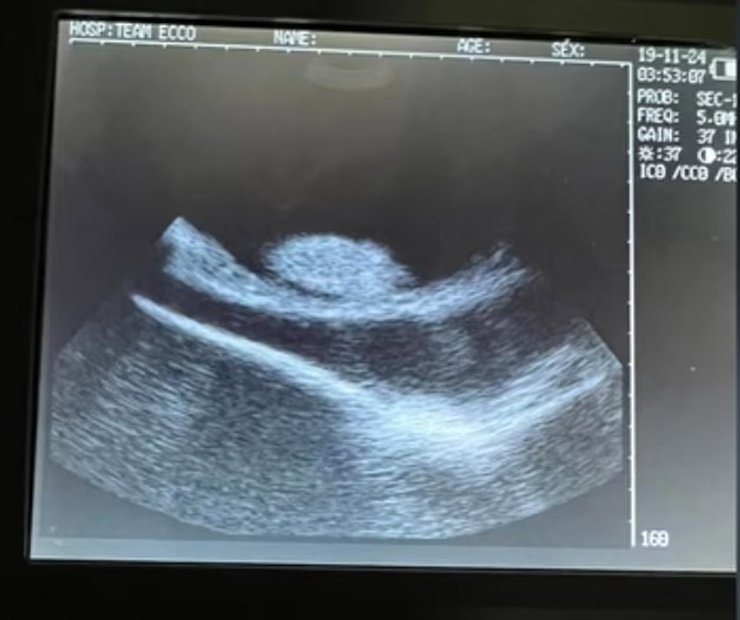

В прошлом месяце ученые опубликовали видео УЗИ Шарлотты, на котором видно, что у нее, вероятно, родится лишь один детеныш, а не четыре, как считалось ранее. Основная проблема заключается в том, что ученые не уверенны, удастся ли детенышу выжить — зачатые посредством партеногенеза животные редко выживают. По словам ученых, непорочное зачатие встречается крайне редко и, по сути, является "последней попыткой" вида выжить в ситуации, когда партнеры недоступны.

скат шарлотта узи

В прошлом месяце Шарлотте сделали УЗИ

Фото: Aquarium & Shark Lab